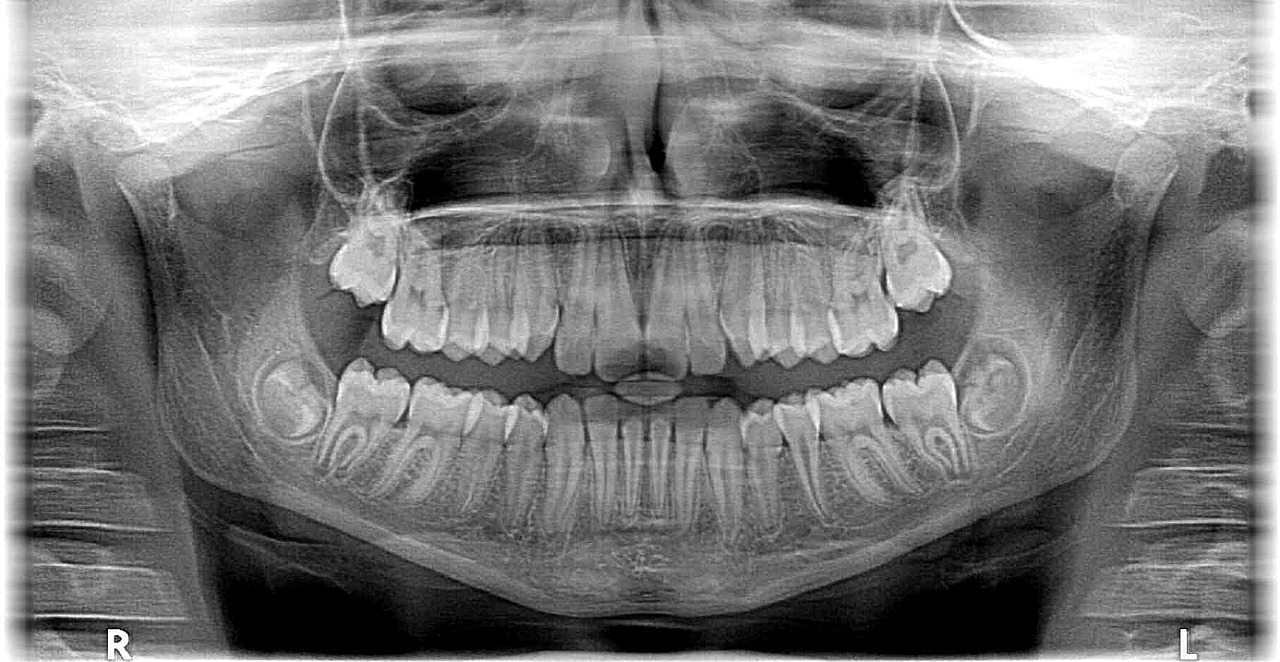

Aus unserer Gesundheitsecke